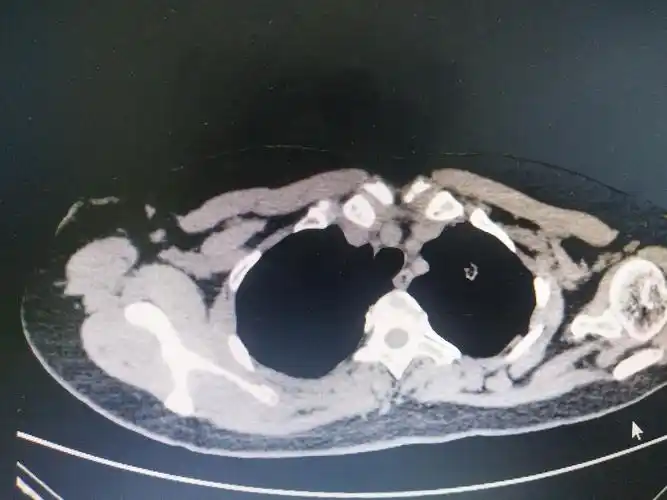

皮肤可见卫星灶,行改良根治术,完整切除了原发肿块及卫星结节

乳房皮肤形成散在分布的质硬结节,即所谓"皮肤卫星结节".

写美篇患者彭某,52岁女性,患者2018年3月确诊为乳腺癌,当时ct发现左上